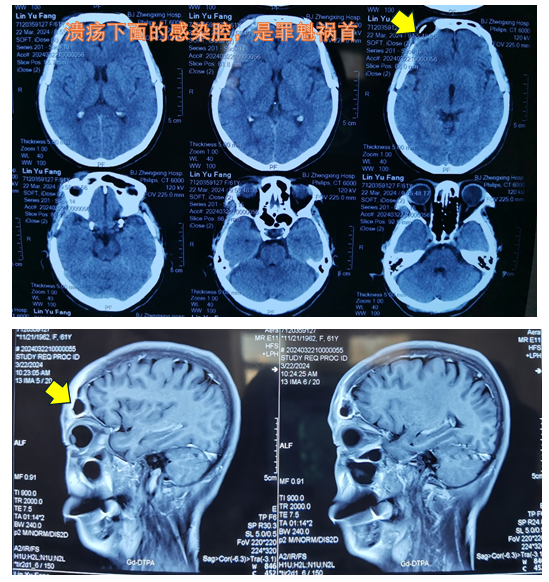

入院之后,傅主任仔细看CT和核磁片子,发现了异常,在额部深处,有一个空腔,自从出现这个腔隙后,老太太的皮肤就开始溃疡不愈合了。傅主任对团队里年轻的医生说:“医生要有耐心,患者的几十张片子,代表了不同时期的治疗方案,有成功的,有失败的。你不去回顾之前的片子,就很难知道之前的治疗为何失败。”